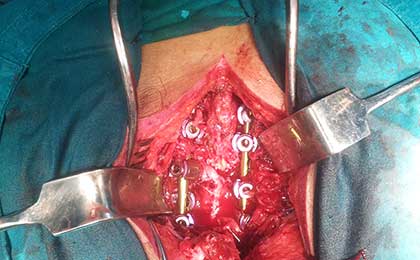

INTRA OP SPINE FIXATION

Spine Fixation Lumbar Spine